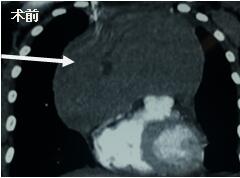

當(dāng)看到病人的CT等外院各項(xiàng)檢查時(shí),我頭皮發(fā)麻,心頭發(fā)怵:巨大的腫塊占據(jù)著整個(gè)縱隔,壓迫心臟,與血管關(guān)系密切,初步考慮侵襲性胸腺瘤、胸腺癌或淋巴瘤等,合并腎功能不全,無(wú)法完整切除,手術(shù)風(fēng)險(xiǎn)大,手術(shù)并不能提高病人長(zhǎng)期生存率,換言之,小伙子等待的是生命的立即終結(jié)。

當(dāng)看到病人癥狀緩解,復(fù)查胸部CT幾近完美,我們那種自豪感油然而生。偶爾去治愈,常常去幫助,總是去安慰,我們深知,小伙子的人生之路并不長(zhǎng),只能深深祈禱他在我們的治療下能走得更遠(yuǎn)一些,能把剩下的日子走的更充實(shí)一些。而我們?cè)谀軌驇椭说臅r(shí)候,別一味地去安慰,永不言棄,是我們這一群胸外人堅(jiān)貞的信念。